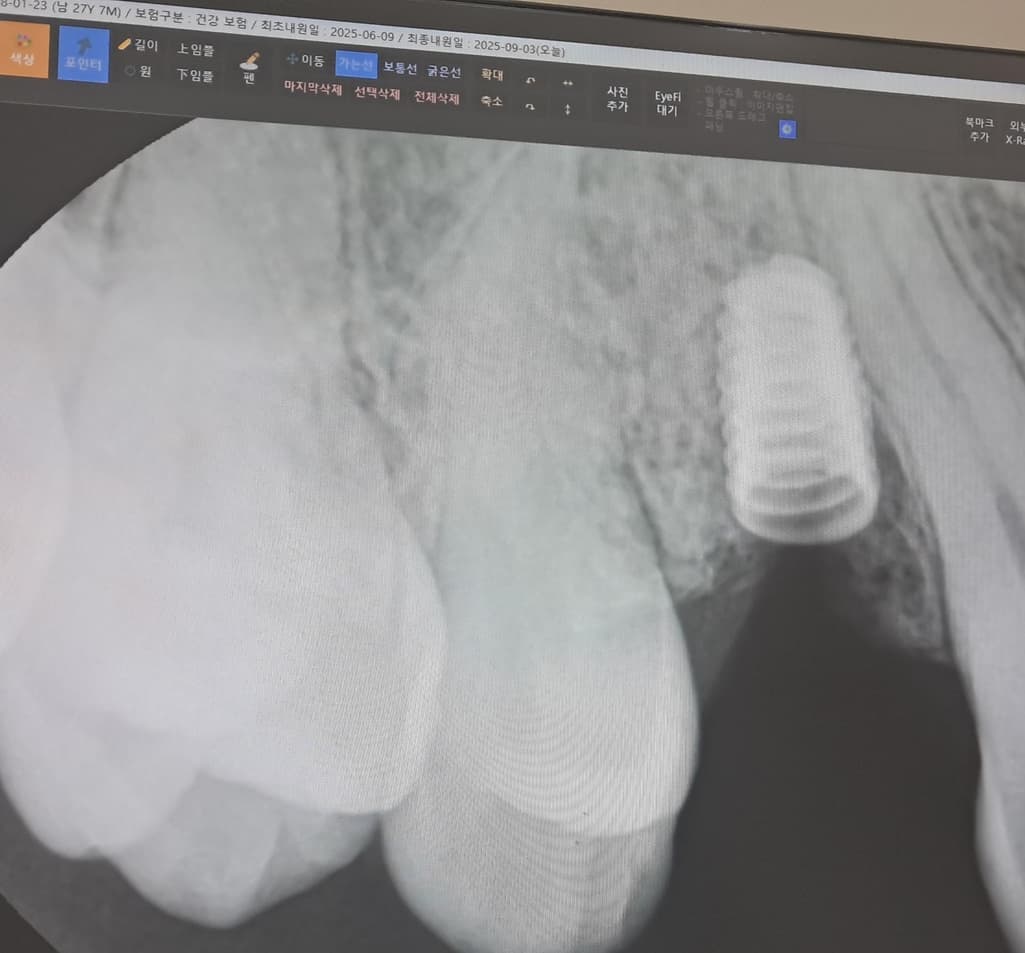

임플란트를 한지는 6년이 지났고 평소에도 자주 음식물이 끼었습니다. 이번에는 그 치아가 흔들려서 치과에 내원하게 됐는데 뼈가 녹았다고 말씀해주셨습니다.

상황상 임플란트 주위염이 발생한 것 같습니다

다시 임플란트 머리 부위 나사 조이는걸로는 처치가 불완전하고 임플란트 뿌리(픽스쳐)를 빼고 다시 수술해야 합니다